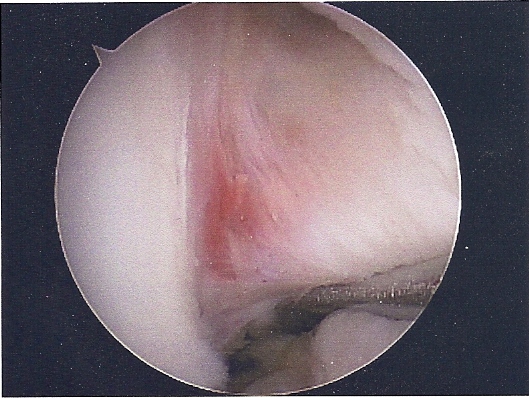

She had ACL replacement surgery on March 28th, using Bone-Patellar-Bone graft from her own patellar tendon. These are the images are scanned from pictures taken by the scope during the surgery. We were supposed to get a DVD of the procedure, but forgot to remind him on the day of the surgery. Oh well...

ACL

NOTCH